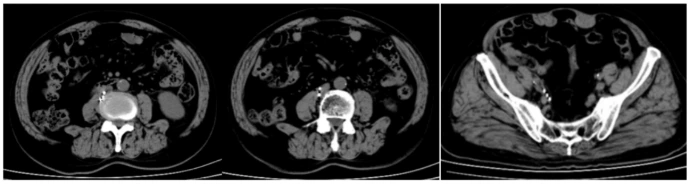

在本治疗中,放射性粒子术后我们对患者进行了为期近36个月的随访观察。2023年1月17日,患者接受了PET-CT(显像剂为FDG),结果显示原腹膜后及右侧盆腔部分淋巴结已消失,残存淋巴结较前缩小,FDG代谢较前明显减低(图1G-I)。2024年5月09日行泌尿系CT示:未见肿瘤明显复发或转移表现(图2)。2025年6月03日行泌尿系CT示:未见肿瘤明显复发或转移表现(图3)。2025年9月05日行泌尿系CT示:未见肿瘤明显复发或转移表现(图4)。随访期间仅行免疫治疗。通过这些检查结果,我们可以得出结论,在单纯免疫治疗效果不佳情况下,125I粒子植入治疗联合免疫治疗在该患者中显示出了良好的疗效。在长达3年的随访中,转移淋巴结的代谢活性降低和体积缩小,代谢活性明显降低甚至消失,尤其是未行放射性粒子治疗的转移灶,且未见新发转移灶,均表明治疗策略的有效性。这些发现为转移性尿路上皮癌的治疗提供了有价值的参考。

图3:2025年6月03日行泌尿系CT示:未见肿瘤明显复发或转移表现

图4:2025年9月05日行泌尿系CT示:未见肿瘤明显复发或转移表现